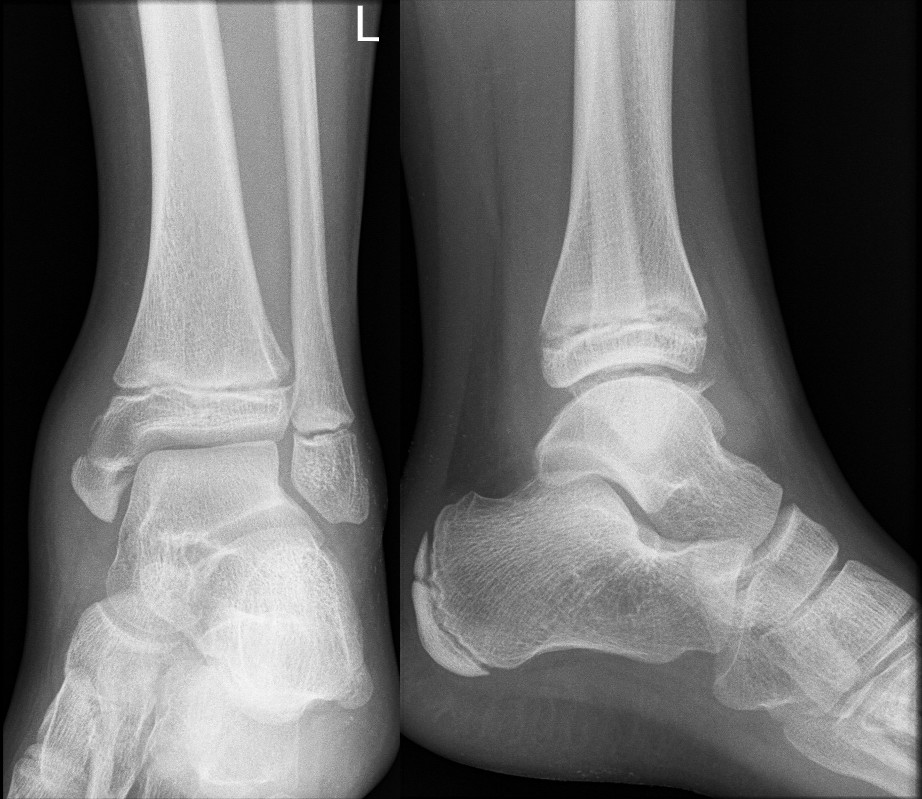

Avulsion of distal fibula

Undisplaced epiphyseal fracture of fibula